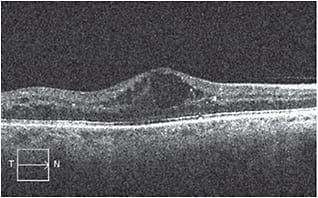

This preoperative SD-OCT image shows significant macular edema with cystoid fluid accumulation in a patient with background DR.